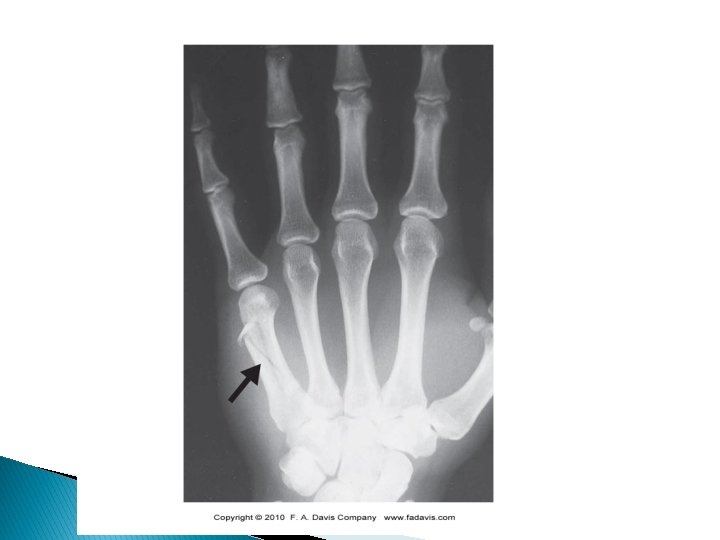

Boxer’s Fracture � Fracture to the 5 th metacarpal ◦ Common incidence after an improperly thrown punch ◦ Depressed 5 th MCP joint � Treatment ◦ Casting or ORIF �Usually casted 6 -8 weeks � Special Tests ◦ Compression test (rotate)

Metacarpal Fractures � Typically fractured due to a compressive force along the bone’s shaft ◦ Such as punching with a fist ◦ Common to hear the bone snap ◦ Gross deformity is common �Immediate swelling ◦ Tenderness along fracture site (pinpoint usually) �crepitus? ◦ Fingers or metacarpal may rotate when hand is attempting to flex ◦ Could happen to any of the metacarpals